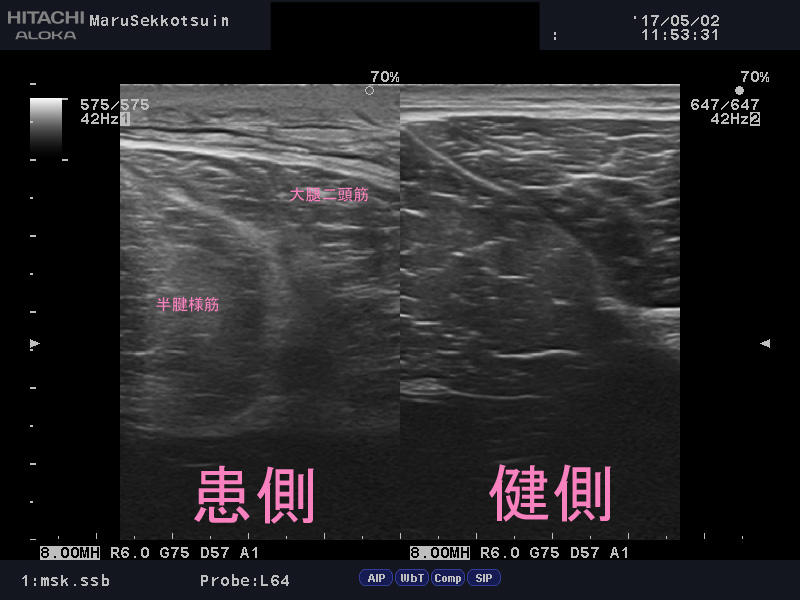

しっかり問診、触診し、エコー検査(超音波画像観察装置)。

ハムストリングス「大腿二頭筋肉離れ」でございました。